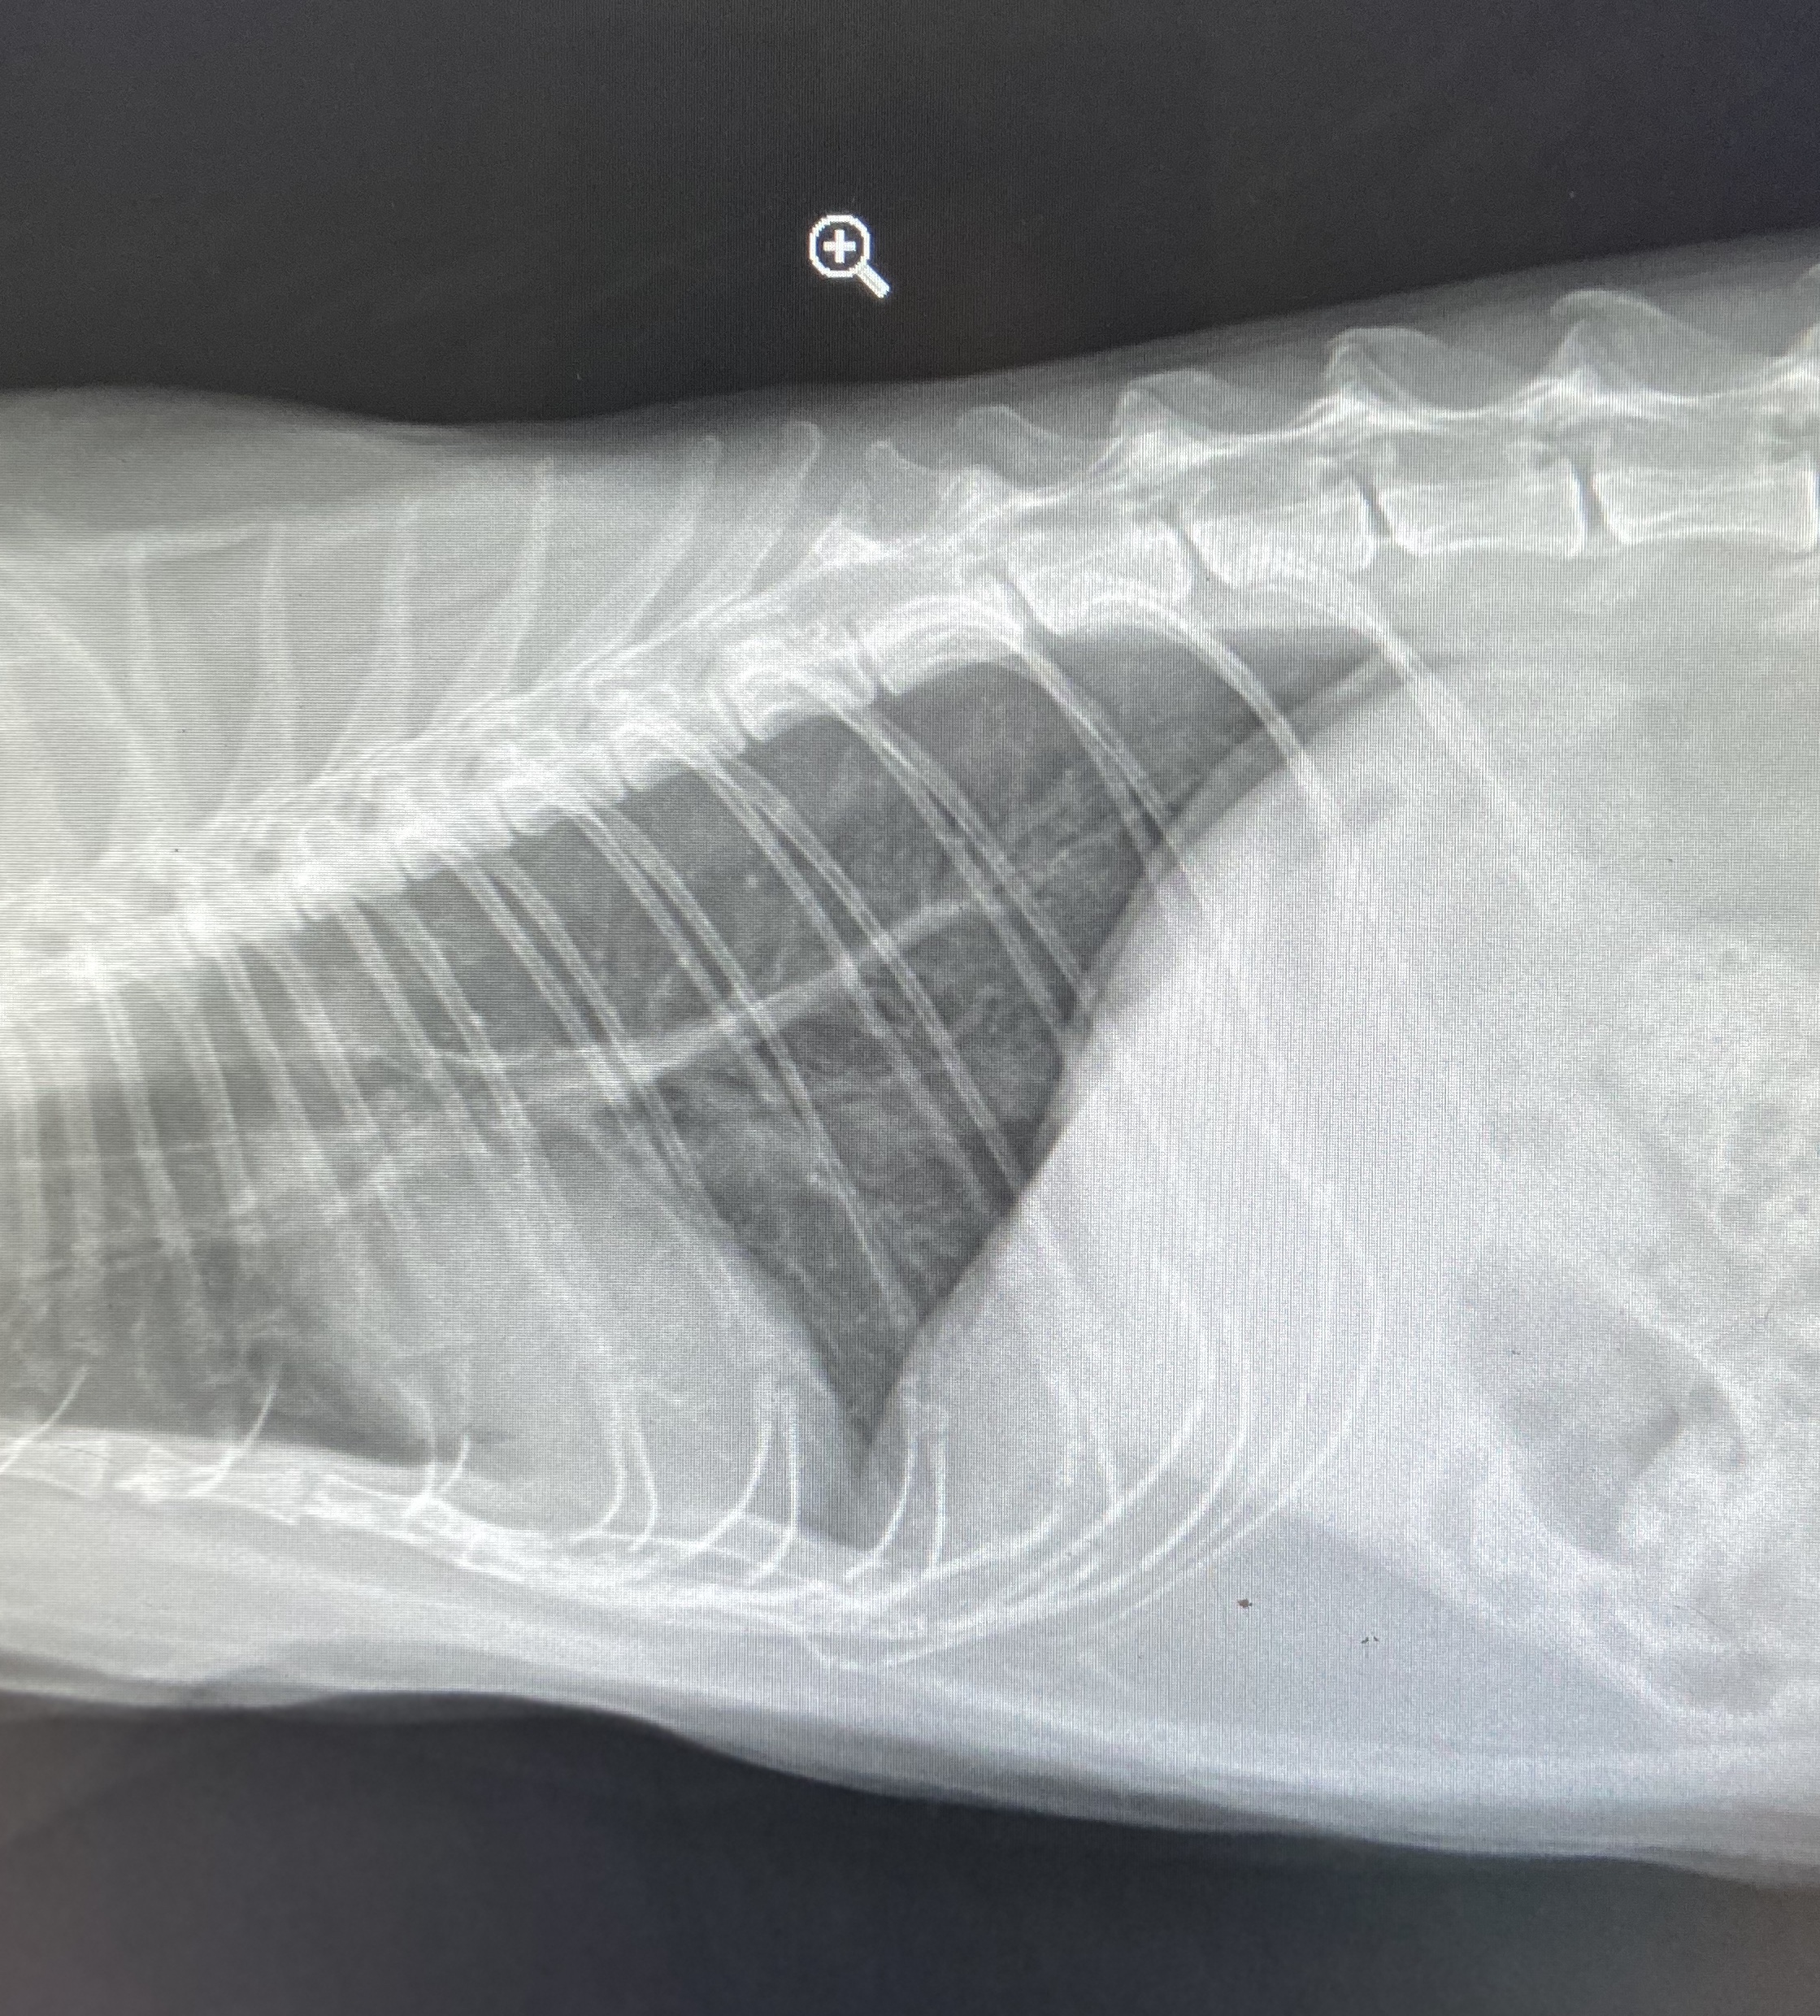

Feline heart, lungs, spine.